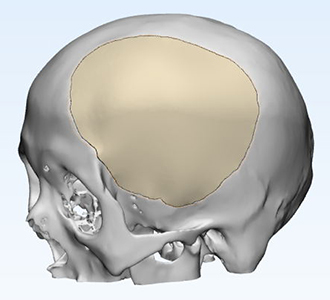

術(shù)前診斷:左側(cè)額顳部顱骨缺損

左側(cè)額顳部顱骨缺損

術(shù)前設(shè)計(jì)方案討論

因患者缺損部位存在腦組織塌陷,皮膚張力可能存在不足,因此給予建議略微降低修補(bǔ)部位peek弧度;設(shè)計(jì)完成后請(qǐng)臨床醫(yī)生確認(rèn)設(shè)計(jì)方案。